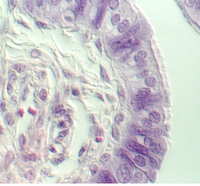

Stratified Cuboidal

Sweat gland ducts are examples of stratified cuboidal epithelium...usually however there are only two layers of cells. They can be found in your slide 25 (thick skin), in the dermis.